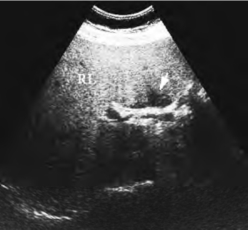

3.部分弥漫性脂肪肝超声表现 内有局限的正常肝组织区,表现为肝内低回声区,其轮廓多较锐,多呈不规则状,无占位效应,周围肝组织回声明显增强,低回声区内常可见到正常血管结构走行(图23-9)。

图23-9 部分弥漫性脂肪肝声像图

部分正常肝组织表现为低回声(箭头所指)